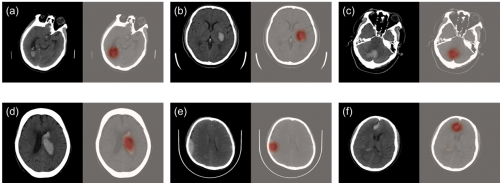

科亞醫(yī)療的“CuraRad-ICH” 是一款專注于對腦卒中進(jìn)行快速腦部出血預(yù)警的AI影像分析處理軟件,可以通過深度學(xué)習(xí)技術(shù)準(zhǔn)確、快速地篩查急性腦出血病例,并直接無縫接入醫(yī)院PACS系統(tǒng), 自動升高腦出血病例的優(yōu)先級,提示影像科醫(yī)生優(yōu)先完成病患的診斷評估,從而有效縮短腦卒中病患的診斷治療時間,挽救生命。

在來自全美48個州296家影像中心的臨床測試中,CuraRad- ICH分析處理軟件達(dá)到了91%的敏感性和93%的特異性,同時平均每次預(yù)警僅耗時43秒,大幅度縮短出血性腦卒中病患的診療時間,受到臨床專家的一致認(rèn)可。